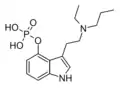

| 4-PO-DET | artificial | 4-OPO3H2 | CH2CH3 | CH2CH3 | 4-phosphoryloxy-N,N-diethyltryptamine | 60480-02-6 |